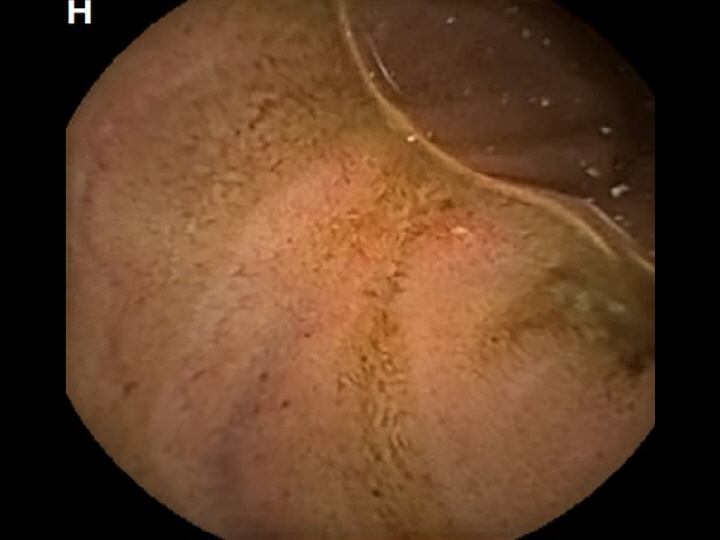

CAPSULE ENDOSCOPY: Crohns Disease: Aphthous Ulcerations in the Small Bowel

Crohns Disease: Aphthous Ulcerations in the Small Bowel. Just click on a picture!

Crohns Disease: Aphthous Ulcerations in the Small Bowel